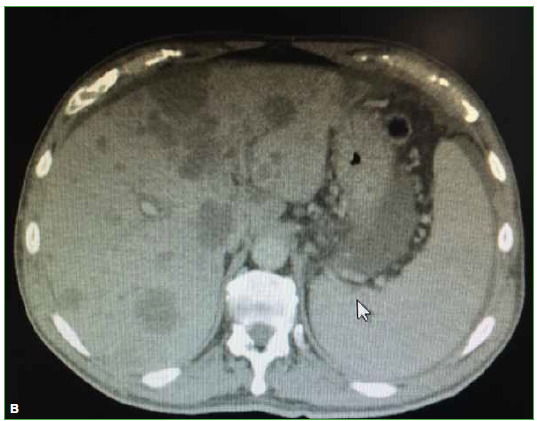

23. Yamaguchi T, Suzuki S, Ishiiwa H, Yamato M, Ueda Y. Schmorl’s node developing in the lumbar vertebra affected with metastatic carcinoma: correlation magnetic resonance imaging with histological findings. Spine 2003;28(24):E503-E505. https://doi.org/10.1097/01.BRS.0000099388.63504.4D

24. Borad MJ, Saadati H, Lakshmipathy A, Campbell E, Hopper P, Jameson G, et al. Skeletal metastases in pancreatic cancer: a retrospective study and review of the literature. Yale J Biol Med 2009;82(1):1-6. https://www.ncbi.nlm.nih.gov/pmc/articles/PMC2660584/

25. Pneumaticos SG, Savidou C, Korres DS, Chatziioannou SN. Pancreatic cancer’s initial presentation: back pain due to osteoblastic bone metastasis. Eur J Cancer Care 2010;19(1):137-40. https://doi.org/10.1111/j.1365-2354.2007.00920.x